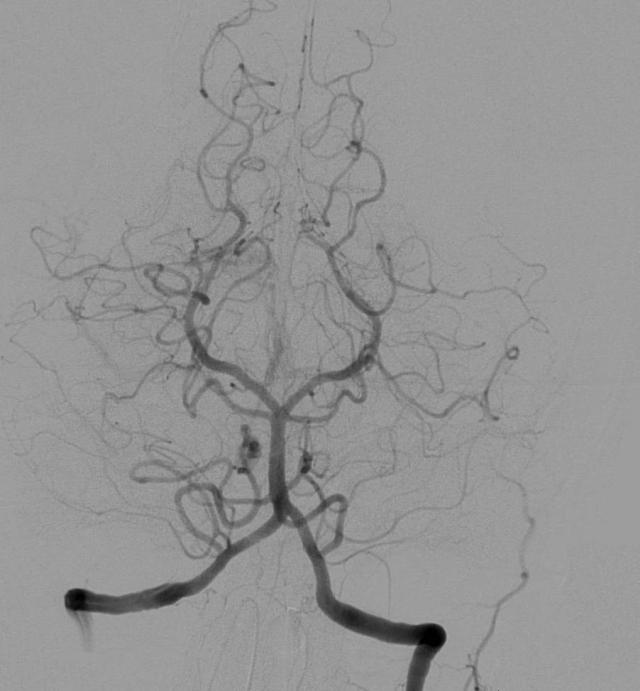

这张照片展示了左侧脑部血管造影,显示有血流;右侧脑部没有血流,就像脑死亡患者那样。© Sparkman Media

脑血管造影显示的椎基底动脉和后脑血液循环前 / 后供血情况,以及威利氏环及其一条供应血管的后视图。© Sparkman Media